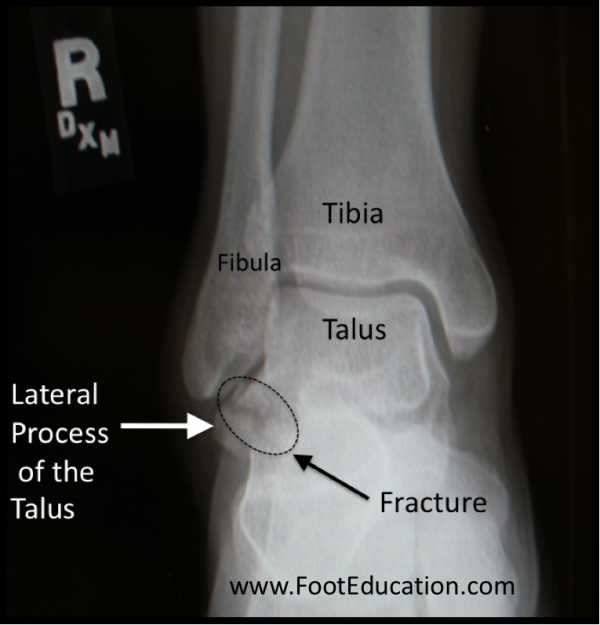

talus fracture